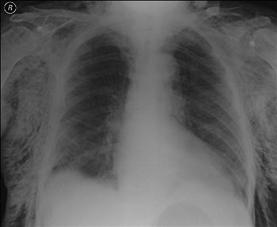

Contuzie pulmonara stanga Contuzie pulmonara dreapta

Contuzie pulmonara dreapta.Imagine CT

(stanga) Contuzie pulmonara (dreapta)